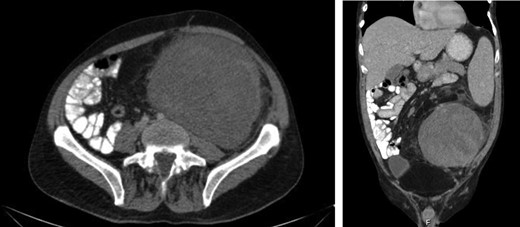

Laboratory work-up revealed a white blood cell count (WBC) of 1.0 K/ul, an absolute neutrophil count of 680, and an absolute lymphocyte count of 310. He was anemic with a hemoglobin of 6.9 g/dl. Rheumatoid factor was elevated to 180 IU/ml. An antinuclear antibody screen was positive at 1:320. Computed tomography (CT) of the abdomen and pelvis showed an enlarged spleen and a large heterogeneous mass in the left abdomen extending into the pelvis (Figs 1 and 2). A bone marrow biopsy showed abnormal CD3+ and CD8+ T-cell lymphocytosis with TCR(beta)+ and CD57+, consistent with the diagnosis of T-cell large granular lymphocytic leukemia.

Axial and coronal CT images demonstrates the large retroperitoneal mass (50 × 33 × 16 cm) displacing bowel, the left kidney, left iliac vessels and bladder to the right.